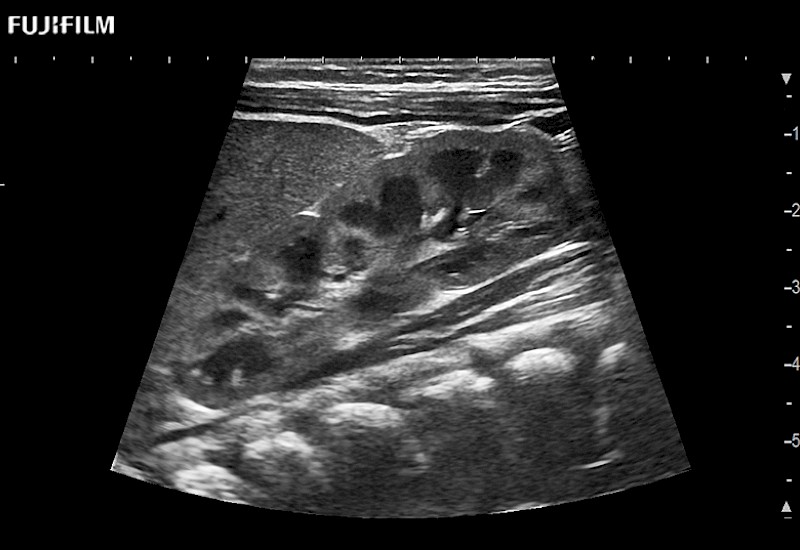

for use during general and laparoscopic procedures: Tumor localization & staging, Ablation, Resection, Biopsy, Transplant, Abdominal exploration, Robotic surgery

Our dedication to Laparoscopic Surgery allows us to offer superior image quality, outstanding system reliability and intuitive use of cutting edge technology.